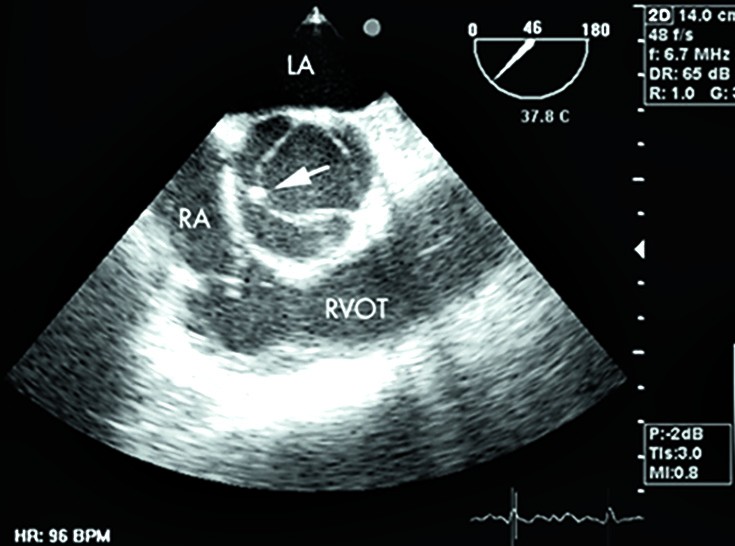

Ehhokardiograafiline meetod südame töö uurimiseks.

Südame aordiklapi ehhokardiograafilisel uurimisel saadud kujutis.